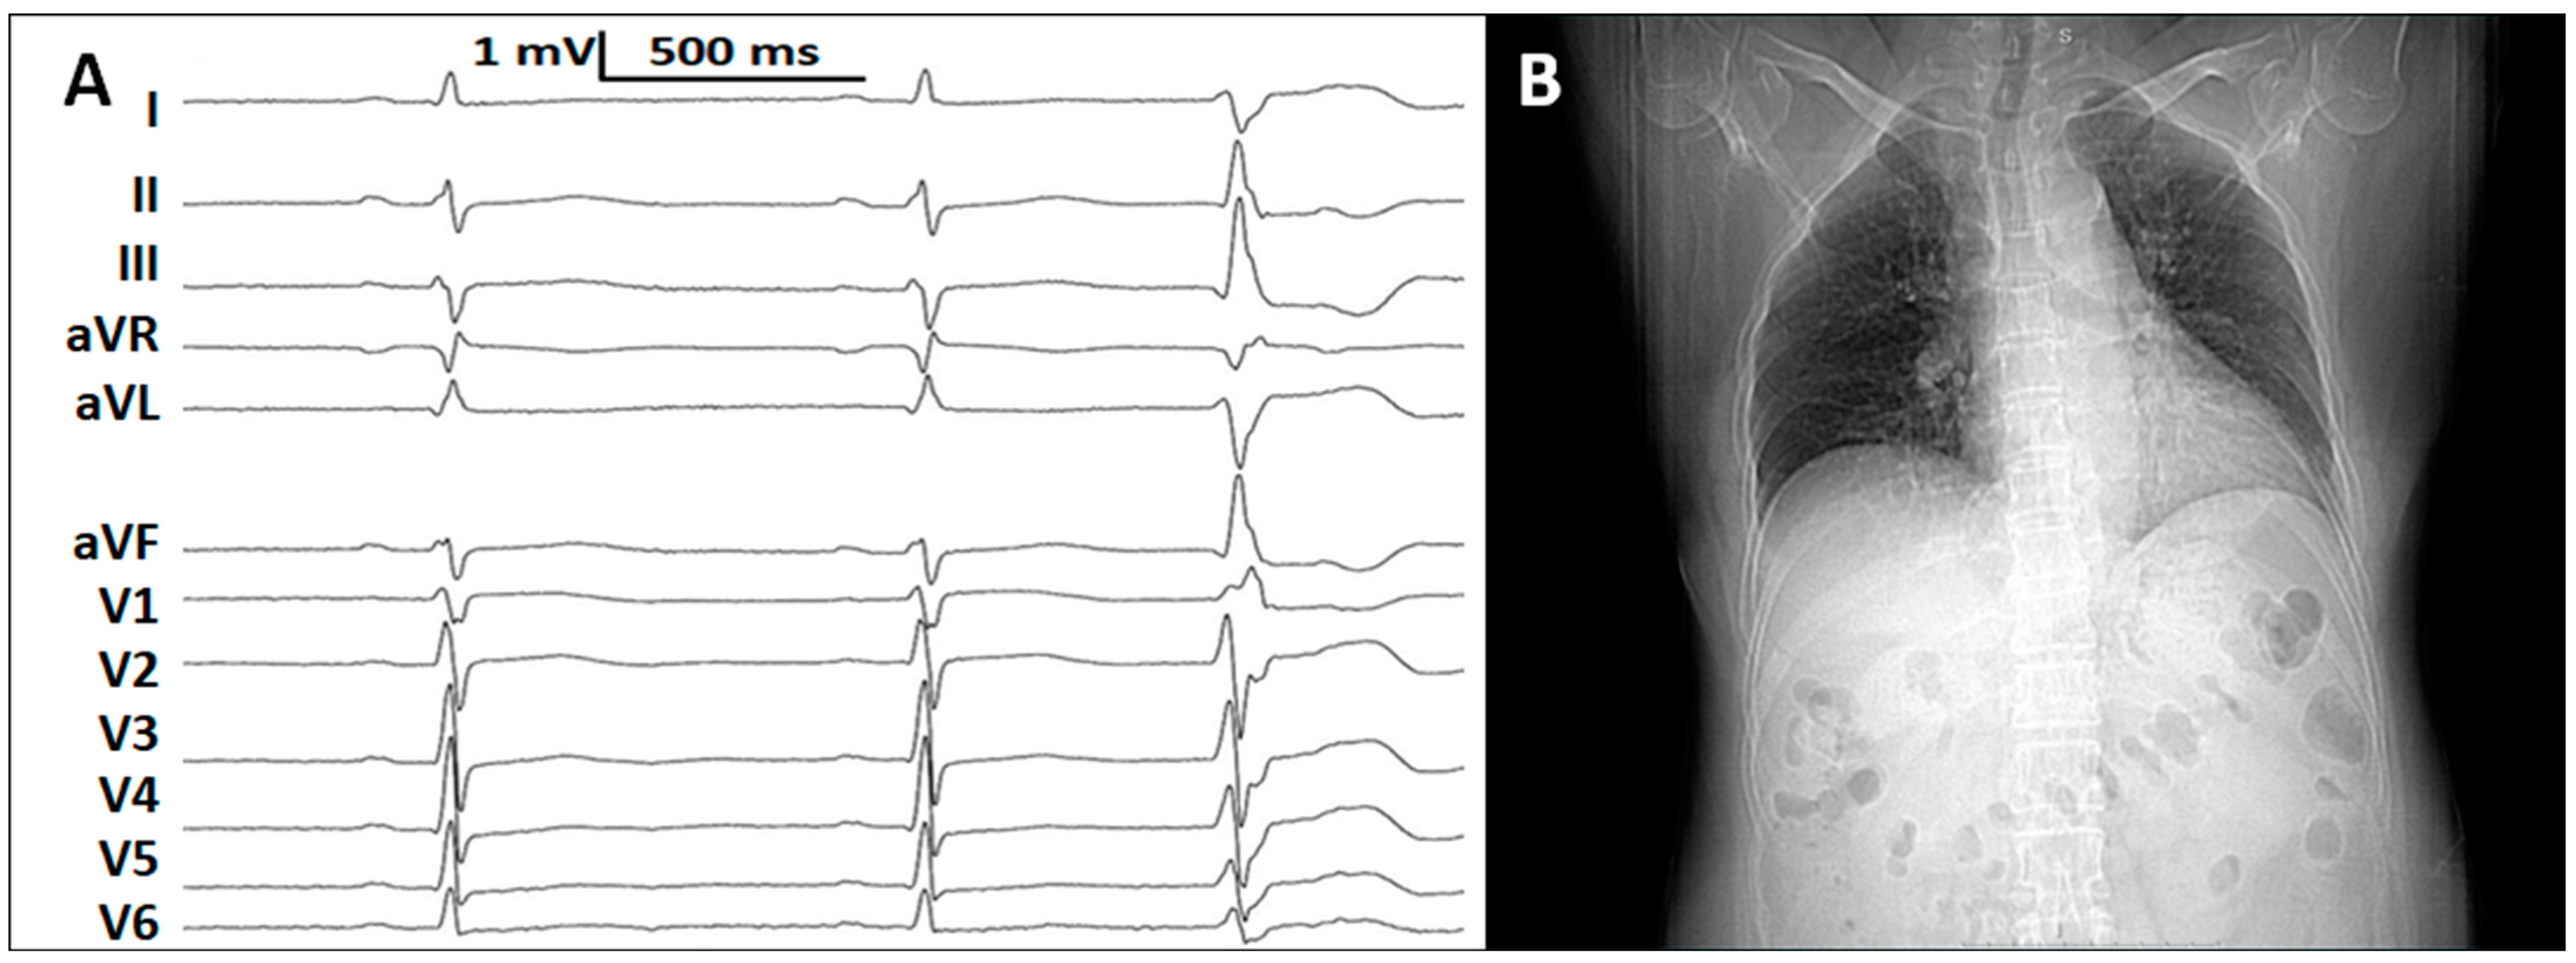

2. Case Report